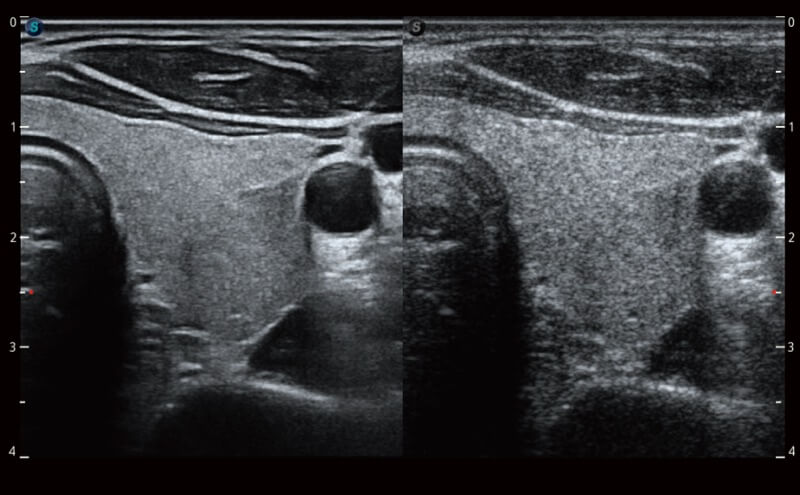

Die Bildqualität liegt immer im Zentrum definierter klinischer Ergebnisse. ELITE liefert eine leistungsstarke und klare Bildgebung, die durch eine leistungsstarke Architektur, hochmoderne Sonden und ausgeklügelte Verarbeitungsalgorithmen erzeugt wird, für ein höheres Maß an Klarheit und Vertrauen.